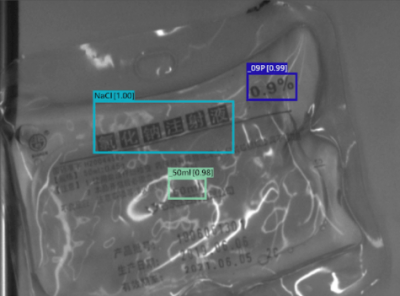

With SolVision‘s segmentation tool, various labels can be identified from sample images to train a visual inspection system capable of classifying information on IV bags based on their distinctive features. SolVision’s advanced AI-based technology is also unaffected by transparent objects, label complexity, or appearance.

Glucose and Sodium Chloride Solution